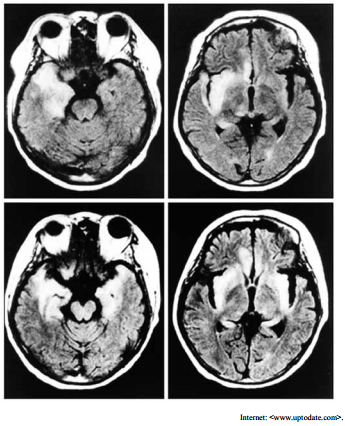

Um paciente com vinte e cinco anos de idade foi admitido em um hospital apresentando, havia cinco dias, febre persistente, cefaleia holocraniana, oscilações de humor e alterações no seu comportamento habitual. O paciente fez uso de analgésicos e antitérmicos, em casa, administrados pela própria família, mas a resposta aos medicamentos foi parcial e temporária. No quinto dia, o paciente estava excessivamente sonolento, e apresentou crise convulsiva tônico-clônica, sendo então levado para atendimento médico de urgência. Acerca desse caso clínico, julgue o item a seguir considerando o exame de imagem mostrado. O agente etiológico da infecção é do mesmo tipo que causa a meningite linfocítica recorrente, também conhecida com meningite recorrente de Mollaret.

Um paciente com vinte e cinco anos de idade foi admitido em um hospital apresentando, havia cinco dias, febre persistente, cefaleia holocraniana, oscilações de humor e alterações no seu comportamento habitual. O paciente fez uso de analgésicos e antitérmicos, em casa, administrados pela própria família, mas a resposta aos medicamentos foi parcial e temporária. No quinto dia, o paciente estava excessivamente sonolento, e apresentou crise convulsiva tônico-clônica, sendo então levado para atendimento médico de urgência. Acerca desse caso clínico, julgue o item a seguir considerando o exame de imagem mostrado. O tratamento do paciente em questão realiza-se à base de corticoide e anticonvulsivante. Em casos de presença de DNA viral no líquor, aplica-se aciclovir.